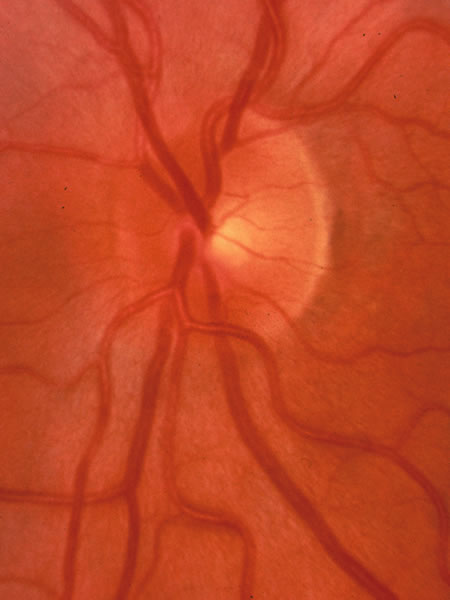

Usually all other forms of optic nerve disease (and inner retinal disease) produce simple atropy of the disc without cupping (Figs. 34 to 36), but occasional cases of cupping have been seen with anterior ischemic optic neuropathy, particularly due to giant cell arteritis (Figs. 37 and 38).

Fig. 37. Swollen optic nerve superiorly during anterior ischemic optic neuropathy caused by giant cell arteritis.

Fig. 38. Same eye after resolution of the attack, with excavation extending to the superior rim of the disc, mimicking the appearance of glaucomatous cupping.